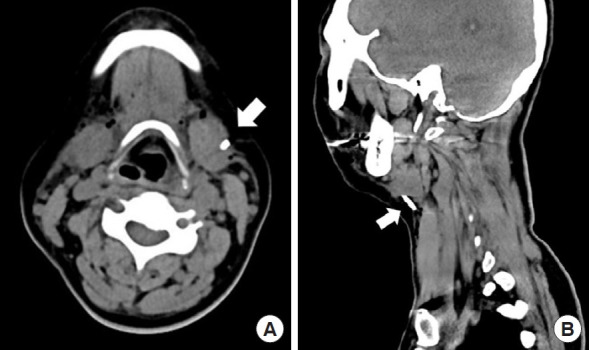

吸脂术是一种广泛应用于各种目的的美容整形手术。先进吸脂技术的使用降低了并发症的风险。然而,它们仍然会意外地发生。在此,我们报告一个罕见的情况下,一个44岁的病人谁经历了一个破裂的套管尖端卡在她的颈部颈面抽脂。该病例强调了通过严格的术前设备检查和适当的仪器维护来预防此类并发症的必要性。此外,当试图去除破损的器械尖端时,在手术前和手术过程中进行影像学检查以精确定位和提取碎片,确保患者安全和成功的结果是至关重要的。

Liposuction is a widely performed aesthetic plastic surgery procedure used for various purposes. The use of advanced liposuction techniques has reduced the risk of complications. Nevertheless, they can still occur unexpectedly. Herein, we report a rare case of a 44-year-old patient who experienced a broken cannula tip lodged in her neck during cervicofacial liposuction. This case highlights the need for vigilance in preventing such complications through rigorous preoperative equipment inspections and proper instrument maintenance. Additionally, when attempting to remove a broken instrument tip, it is crucial to perform imaging examinations both before and during the procedure to precisely locate and extract the fragments, ensuring patient safety and a successful outcome.